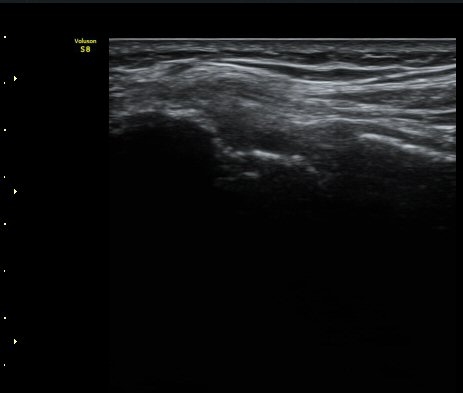

³»»ó°ú Á¾´Ü¸é°Ë»ç»ó  ³»ÃøºÎÀδë Àú¿¡ÄÚ ºÎÁ¾°ú ³»»ó°ú ÀÎ´ë ºÎÂøºÎ ÇÇÁú°ñÀÇ ºÒ±ÔÄ¢º¯È­¿Í

°ñÆíÀÌ °üÂûµÇ°í(±×¸² 1, 2, 3, 4) ÀÌ·±¼Ò°ßÀº °ÇÃø°ú ºñ±³ÇÏ¸é ´õ¿í ¶Ñ·ÈÇÔ(±×¸² 5, 6).